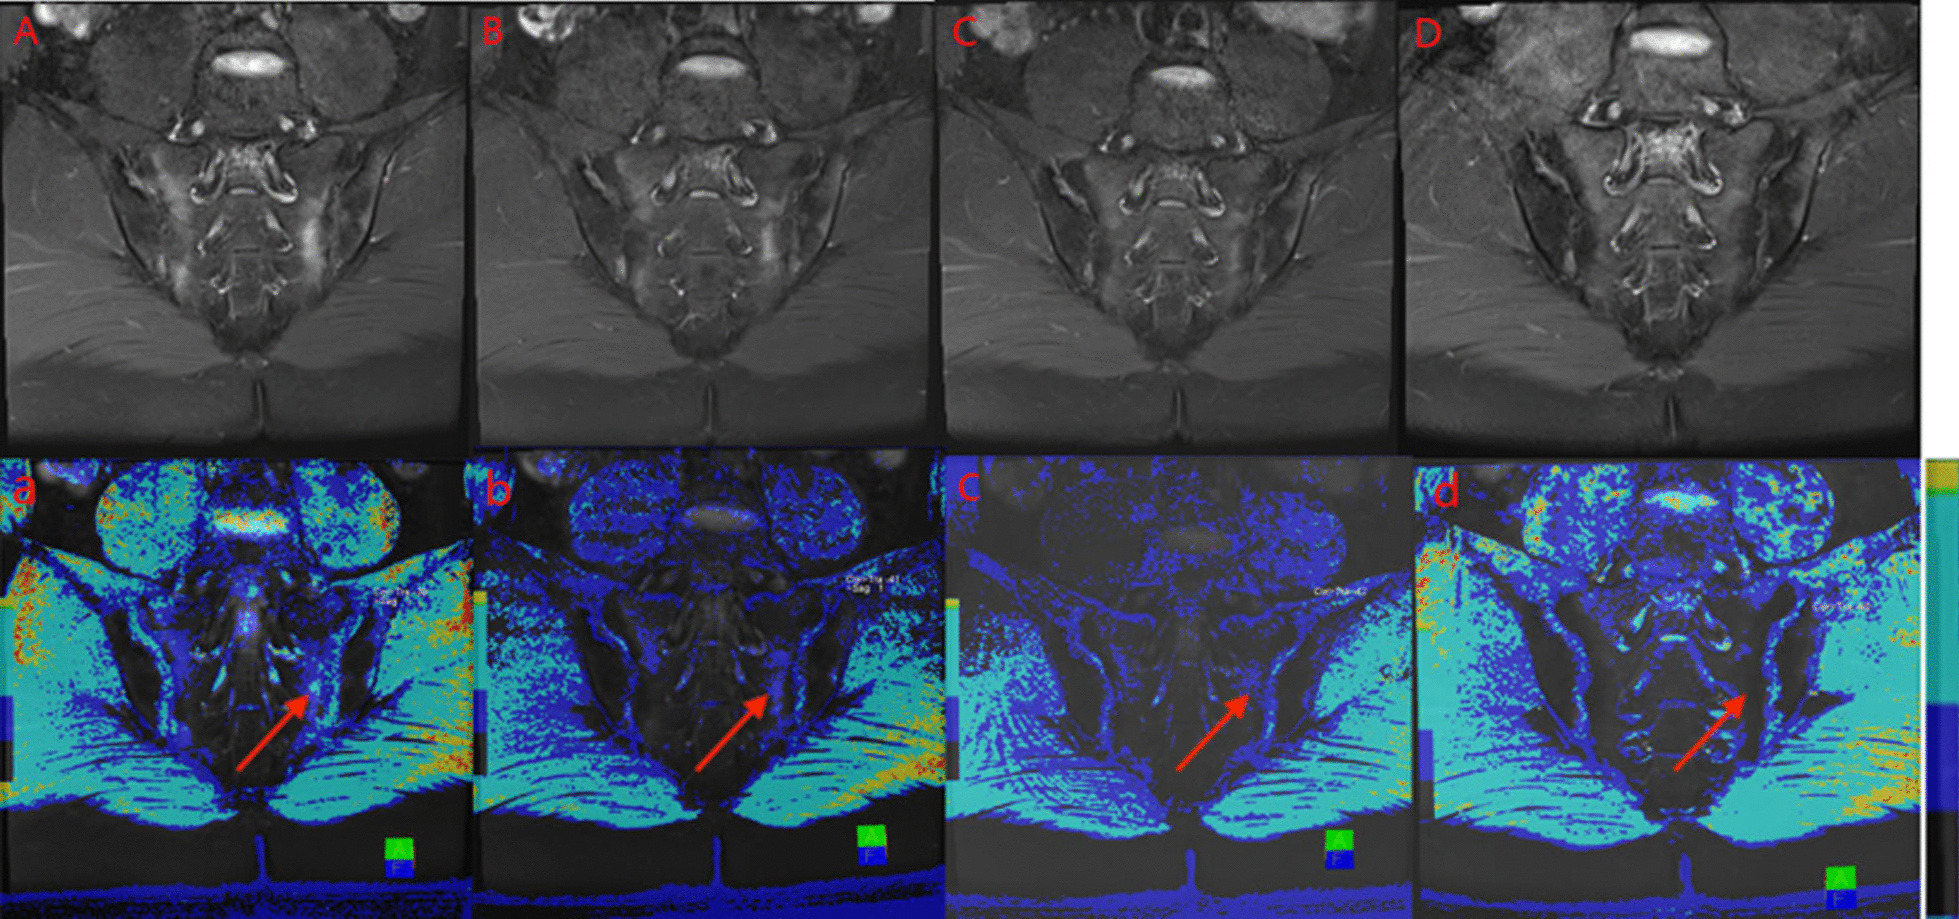

Fig. 3.

A male, 24 years old, HLA-B27: ± , ASDAS-CRP:3.8, belongs to the very high disease activity group. Depending on the different treatment cycles, these are pre-treatment (A,a), 3 weeks (B,b), 6 weeks (C,c) and 12 weeks (D,d) after treatment, respectively. A–D. Fat suppression PDWI sequences show the decreasing of sacroiliac bone marrow signal, gradually. the ASDAS-CRP score decreased with the increase of the treatment cycle (2.6, 1.6, 1.0, 0.6). a–d. T1-mapping pseudo-color diagrams also demonstrate the decreasing of the regions of interest T1-mapping value, gradually. (956.43, 780.73, 604.73, 349.27 ms).

Comparison of decreasing rate of T1 mapping value in the subchondral bone marrow area of the treatment group

In the treatment group, signal intensity of bone marrow under sacroiliac joint surface decreased in varying degrees among pre-treatment, 3-weeks, 6-weeks, and 12-weeks treatment groups. The PDWI sequence showed that the signal of subsacroiliac bone marrow decreased in different degrees (Fig. 3A–C). The value of T1 mapping showed a downward trend (Fig. 3a–c), and the value of T1 mapping decreased synchronously with the value of ASDAS-CRP (Fig. 4). Using the Spearman rank correlation analysis, the correlation coefficient between T1 mapping value and ASDAS-CRP score was 0.713, P < 0.001. Compared with the paired T-test, the difference of T1 mapping value in each treatment week was statistically significant, T (7.311, 5.596, 6.083), P < 0.001. Compared with the previous cycle, the decrease of bone marrow T1 mapping value in the 3-week, 6-week, and 12-week treatment groups were (426.60 ± 260.95, 224.47 ± 179.39, 124.92 ± 91.85), and the average decreasing rate of T1 mapping was (0.360 ± 0.203, 0.551 ± 0.129, 0.658 ± 0.098). Figure 4 the values of T1-mapping and ASDAS-CRP in the treatment group decreased synchronously pre-treatment, 3 weeks, 6 weeks and 12 weeks after treatment.